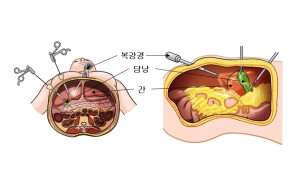

그러나 최근 복강경 담낭 절제술이 보편화되면서 담낭 절제술 후 우연히 발견되는 조기 담낭암의 비율이 전 세계적으로 증가하고 있습니다. 우리나라의 경우에는 이와 함께 건강검진의 시행으로 인해 수술적 절제를 할 수 있는 담낭암 진단이 증가하고 있습니다. 담낭암은 현재까지 수술에 의해서만 완치가 가능한 종양이며 병기에 따라 수술 치료 원칙이 달라지므로, 정확한 병기 진단과 이에 따른 적절한 수술적 치료가 시행되어야 합니다.

암세포가 담낭의 점막이나 근육층 내에 국한된 경우에는 담낭 절제술로 치료할 수 있습니다. 2기나 3기와 같이 암이 진행된 경우에는 간 부분 절제 및 주위 림프절을 포함한 광범위 절제술을 시행합니다. 4기의 경우 간혹 간췌십이지장 절제술 및 간인대췌십이지장 절제술을 시도하지만 완치율은 높지 않습니다.